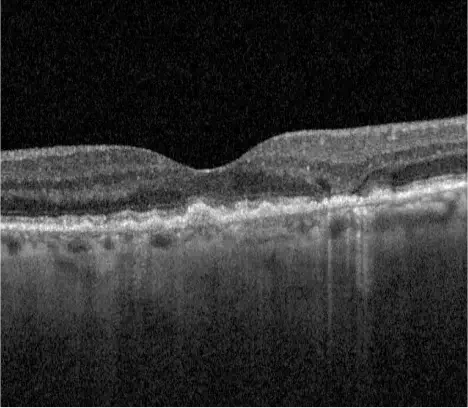

Neovascular AMD

- In clinical trials, use of IZERVAY was associated with increased rates of neovascular (wet) AMD or choroidal neovascularization (7% when administered monthly and 4% in the sham group) by Month 12. Over 24 months, the rate of neovascular (wet) AMD or choroidal neovascularization in the GATHER2 trial was 12% in the IZERVAY group and 9% in the sham group. Patients receiving IZERVAY should be monitored for signs of neovascular AMD.